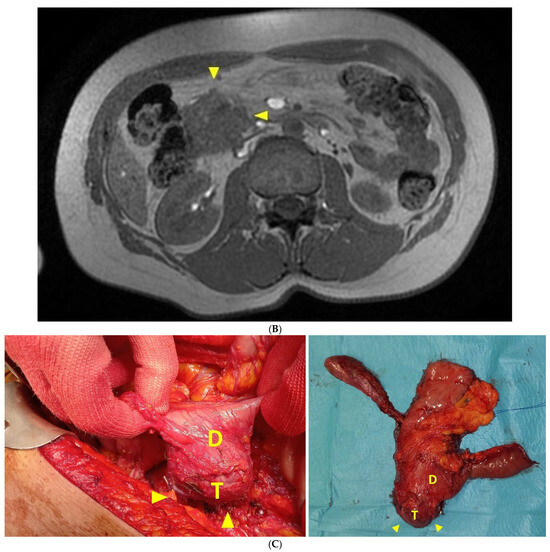

2.1. Case Report 1

2.2. Case Report 2